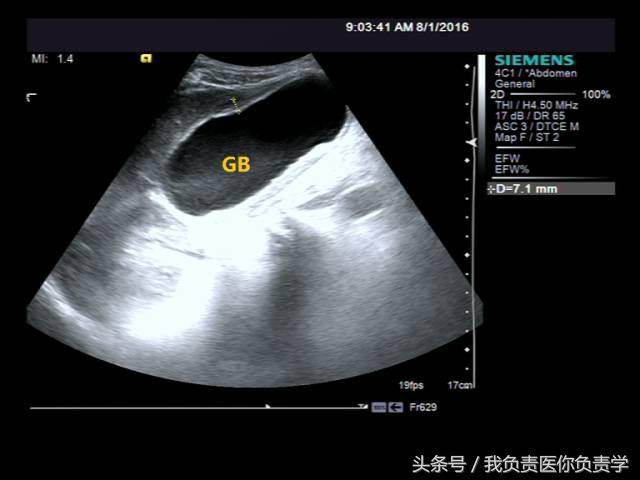

典型病例 1

患者男,64岁,因右上腹疼痛半月余就诊。查体发现右上腹部轻压痛,无发热。超声检查所见如下:

图1示胆囊增大,囊壁增厚,囊内透声差